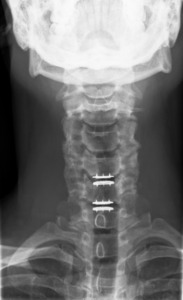

The subject was seen in PT for 14 sessions spanning 16 weeks. The initial evaluation session was one hour long and follow up sessions were 30 minutes in length. PT interventions included manual therapy (soft tissue and joint mobilization), therapeutic exercise (targeting cervical spine, thoracic spine and upper extremity to address mobility and strength), and weightlifting body mechanics education. Radiographic confirmation of prosthesis placement and healing was monitored at postoperative weeks six and 12 (Figures 4-5).

Improvements were noted with NDI (14% to 0%), PSFS (3.4/10 to 10/10), SF-12 PCS (+5.4) and SF-12 MCS (+25.7), and NPRS (2/10 to 0/10). Cervical AROM improved in extension 55-60 degrees, total rotation 60-75 degrees, total lateral flexion 20-45 degrees, and DNF endurance 5-35 seconds. Postoperative radiographs at week 6-12 no evidence of prosthesis malpositioning, displacement, subsidence or heterotopic ossification.